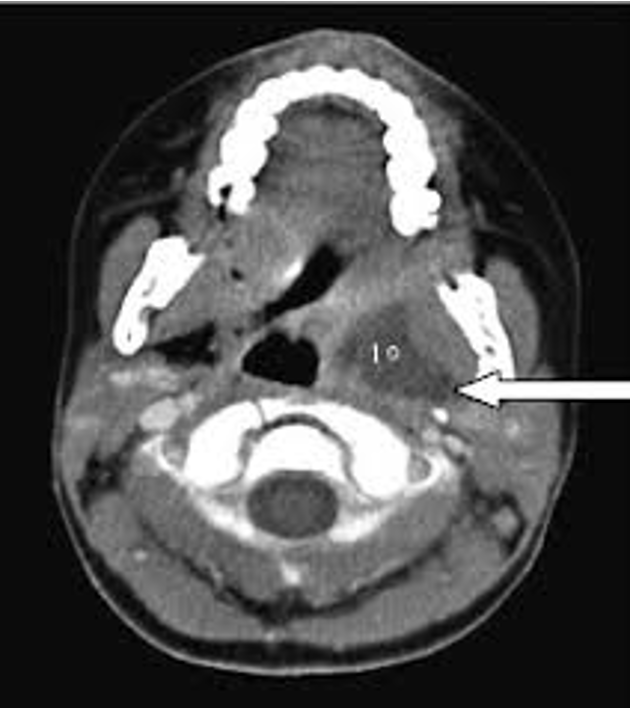

Source of the infection:

- odontogenic

- tonsils,

- parotid